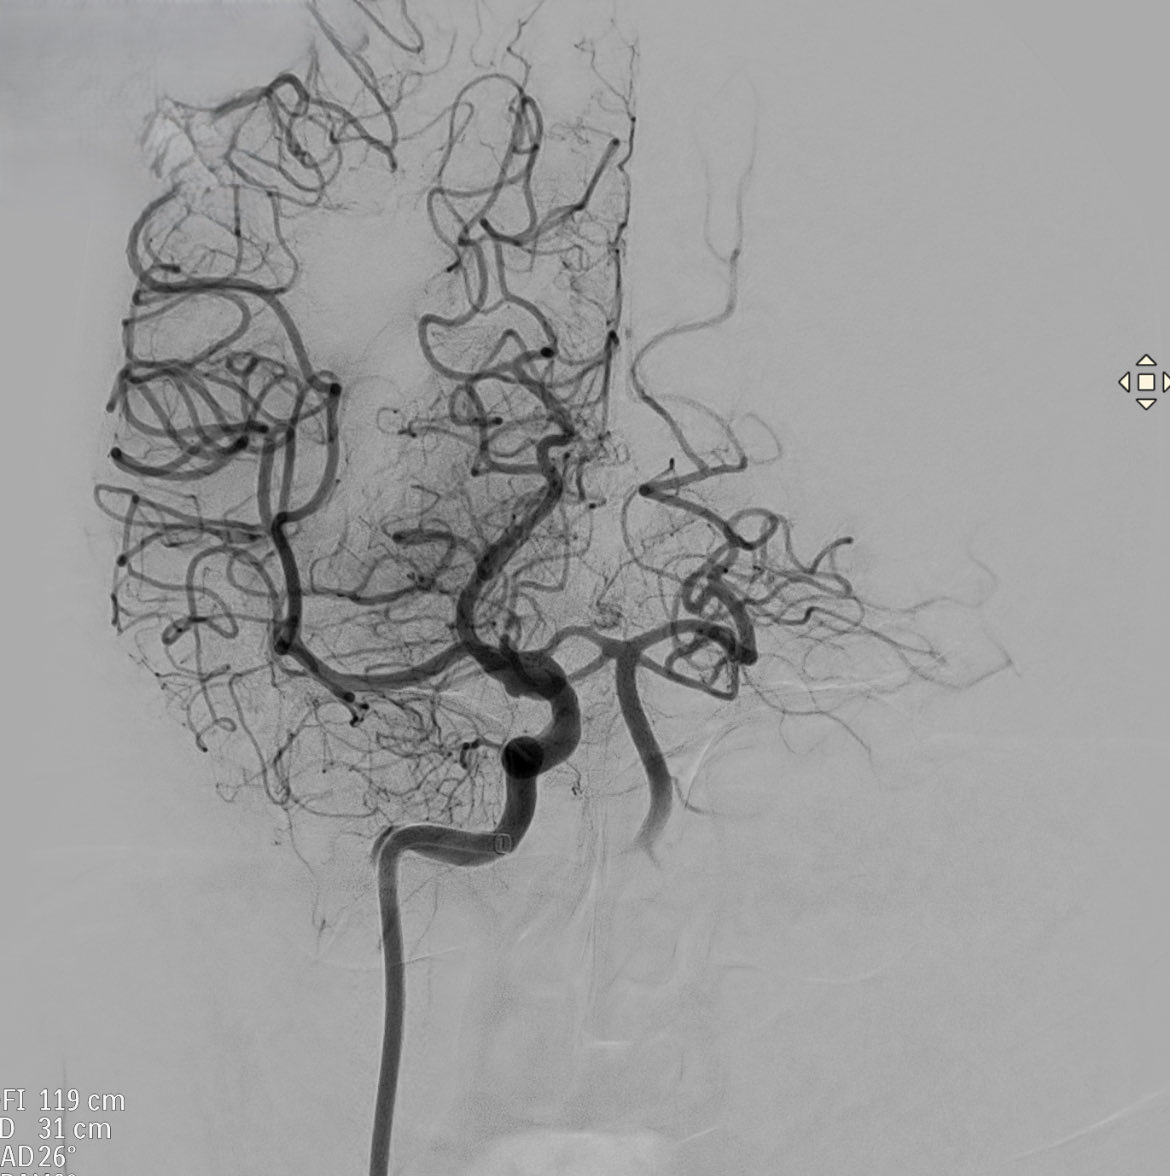

Patient admitted for ischemic stroke.

This is the arteriography prior to mechanical thrombectomy

Which artery is occluded ?

What anatomical variant is suspected ?

#Stroke

#Thrombectomy

#Neuroanatomy

#Anatomicalvariants

#Neurotwitter